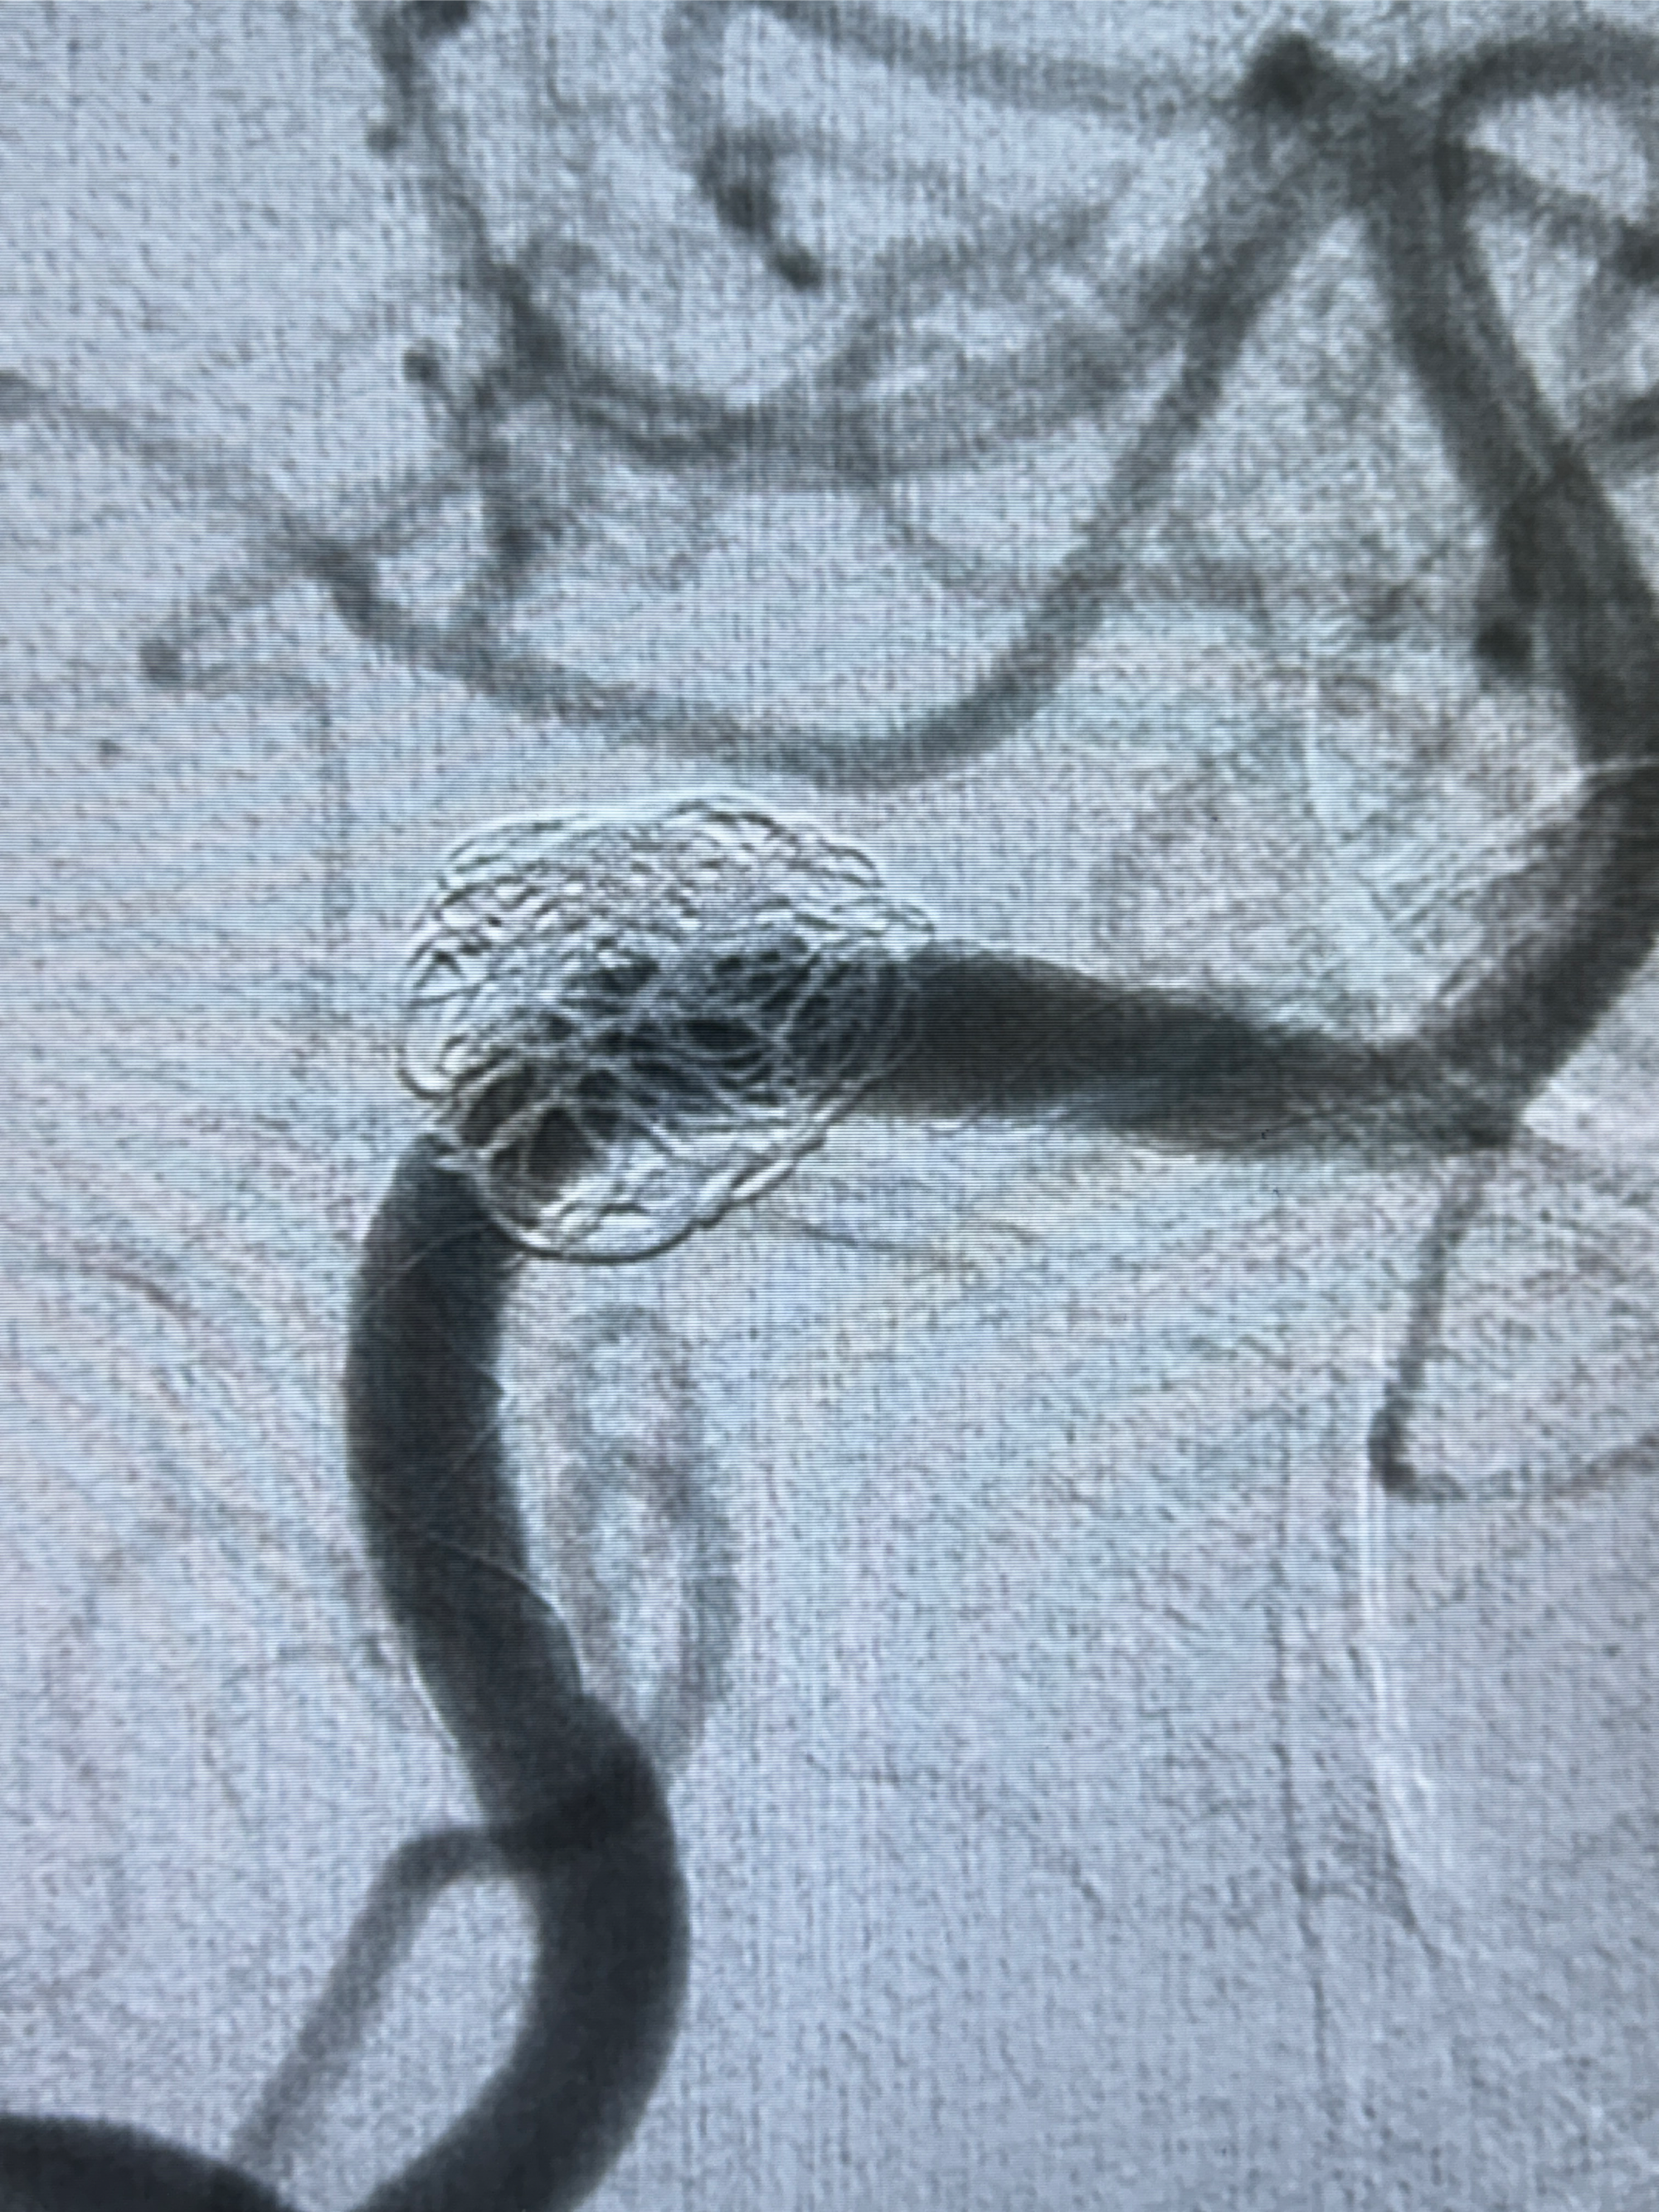

现病史:患者诉2022.06.24因“检查发现颅内动脉瘤”就诊于华山医院查全脑血管造影诊断右侧椎动脉夹层动脉瘤(14.86*12.02mm),随后在全麻下行支架辅助栓塞术(LEO,本人诉2枚支架),术顺,术后予以阿司匹林、氯吡格雷、阿托伐他汀钙片对症治疗;术后3月因下肢淤青停用氯吡格雷,患者近2月开始出现发作性右侧枕部隐痛不适,持续时间约几分钟,着凉可诱发,余一般情况可,目前服用阿司匹林1片qd治疗中,为复查脑血管造影收入我科。

2024-01-08DSA:右侧椎动脉V4段夹层动脉瘤双支架辅助弹簧圈栓塞术后

患者支架辅助治疗后18个月,动脉瘤痊愈